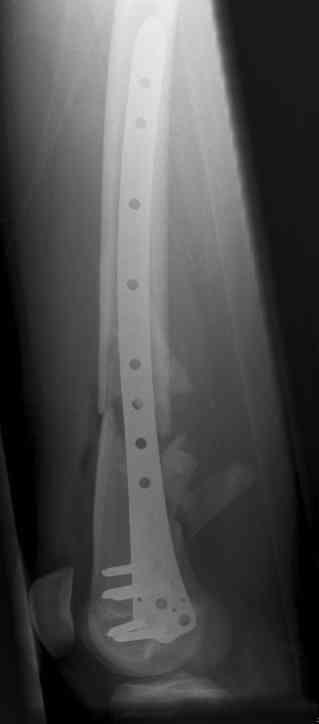

16 yr old boy, high energy motorcycle trauma trauma in July 2005 with:

- hip dislocation + acetabular fracture L

- distal femoral fracture L

- tibial shaft fracture L

- metatarsal fractures L

july 05: LISS femur, LCP plate tibia, double recon. plate post. acetabulum

oct 05: cancellous bone graft femur

aug 06: blade plate + bone graft

nov 06: revision blade plate

feb 07: retrograde nail + bone graft + BMP

may 07: dynamisation nail

sept 07: locking screw removal (max. dynamisation reached)

nov 07: persistant non-union distal femur; other fractures healed uneventfully.

All with gradual/partial weightbearing etc. Currently 50-100% weight bearing, no pain.

Soft tissues are intact. No smoking or diabetes.CRP <2